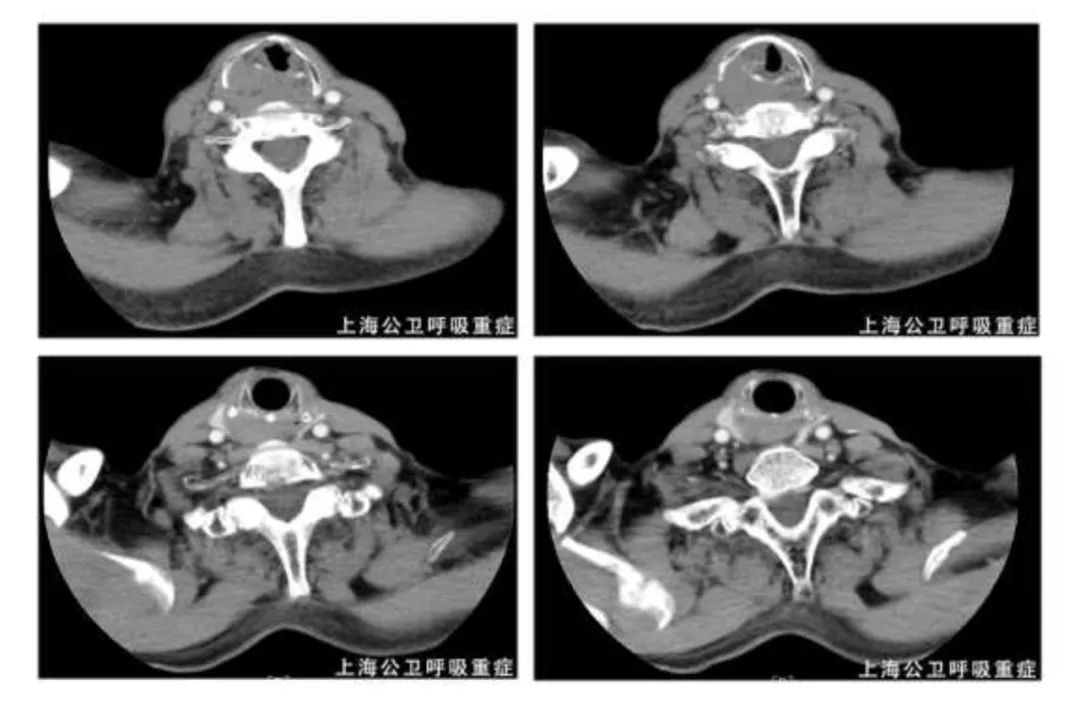

2020.10.22胸部CT增强示:左上肺尖后段、左上肺前段、左下肺前基底段及外基底段实性结节,左肺散在炎症,左侧胸膜局灶性增厚,左侧胸腔少量积液,左下肺部分膨胀不全;MT待排,请结合临床并进一步检查。左侧肺门淋巴结肿大。两上肺胸膜下小肺大泡。

2020.11.30复查胸部CT示:左肺上叶尖后段、左肺下叶外基底段及前内基底段实性结节;左肺少许炎症;左侧少量胸腔积液;左侧胸膜增厚;较前2020-11-26片,左肺下叶前内基底段病灶略减小,左肺下叶外基底段新发实性结节,左侧胸腔积液略增多,左肺上叶尖后段病灶相仿。左肺门淋巴结肿大,与前片相仿;两上肺胸膜下小肺大泡。气管右后方增厚软组织影,建议颈部MRI增强检查。

2020.12.01颈部CT增强示:右侧喉部软组织占位,两侧颈部多发肿大淋巴结,部分融合——考虑MT伴颈部淋巴结转移可能大,请进一步检查。